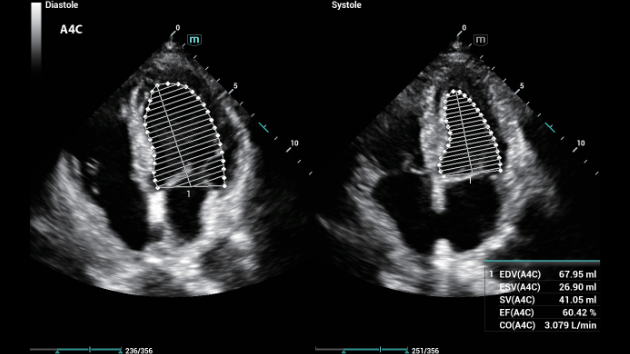

De Consona biedt nieuwe en concrete oplossingen die effici?nt helpen bij het stellen van een vlotte diagnose voor veel verschillende soorten pati?nten.

Ongeacht of u werkzaam bent in een ziekenhuis of kliniek, of uw vaardigheden aanscherpt op het gebied van algemene beeldvormingstoepassingen, vrouwengeneeskunde of cardiovasculaire specialismen, in deze serie vindt u zeer krachtige hulpmiddelen waarmee u aan kop kunt blijven.

Uitgebreide?oplossingen voor beeldvorming aangestuurd door ZST?+

Het ZST+?platform is een buitengewone innovatie en revolutie in de wereld van echografie. Het transformeert echografiegegevens van conventionele bundelvorming naar kanaalgegevensverwerking. Het overwint de traditionele afweging tussen ruimtelijke resolutie, temporele resolutie en weefseluniformiteit, en levert een uitzonderlijke beeldkwaliteit voor oneindige beeldvormingsoplossingen met non-stop verbeteringen.